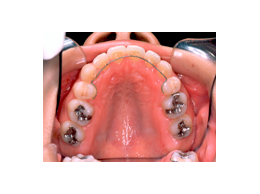

叢生 治療前 上顎

この患者さんでは、上下左右の歯を計4本抜きましたが、それでももスペースが足りませんので、さらに顎の形を変えて並べ替えました。

抜歯する歯は、変なところに生えていた犬歯ではなく、4番目の歯(=第一小臼歯)です。犬歯を抜くと、顎運動や歯並びの見た目、口元のふくらみがなくなることで老けて見えるなど、いろいろな悪影響があります。従って、できるだけ抜歯は避けたいのです。

歯を抜いたスペースを利用して、残りの歯をきれいに並べ替えてゆきます。この患者さんの場合は、抜いたスペースはほとんど余りませんので、意外に早く治療が終わりました。